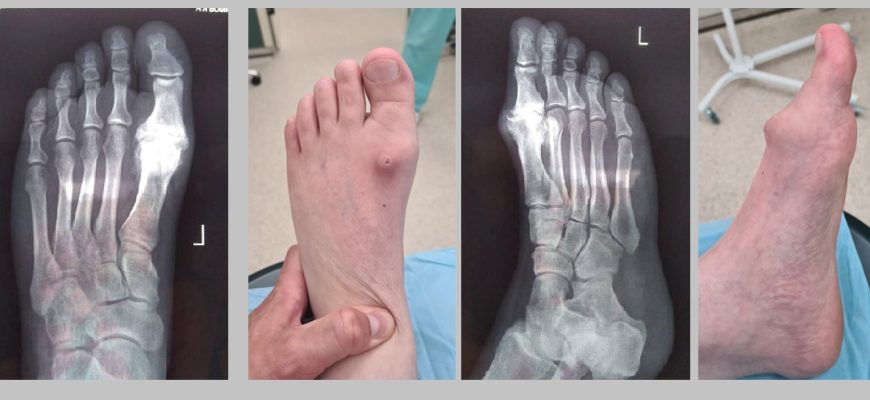

Изменения стопы при артрозе: что происходит и как справиться Когда мы слышим о артрозе, большинство из нас сразу представляет себе боли в коленях или бедрах․

Изменения стопы при артрите: что ожидает вас и как помочь своему организму Когда мы сталкиваемся с диагнозом артрит, мир вокруг кажется немного меняется.

Изменения стопы при артрите: что нужно знать и как справиться с проблемой Когда речь заходит о воспалительных заболеваниях суставов, таких как артрит

Изменения стопы при артритах: как сохранить движение и комфорт Когда речь заходит о таких заболеваниях‚ как артрит‚ мы зачастую задумываемся